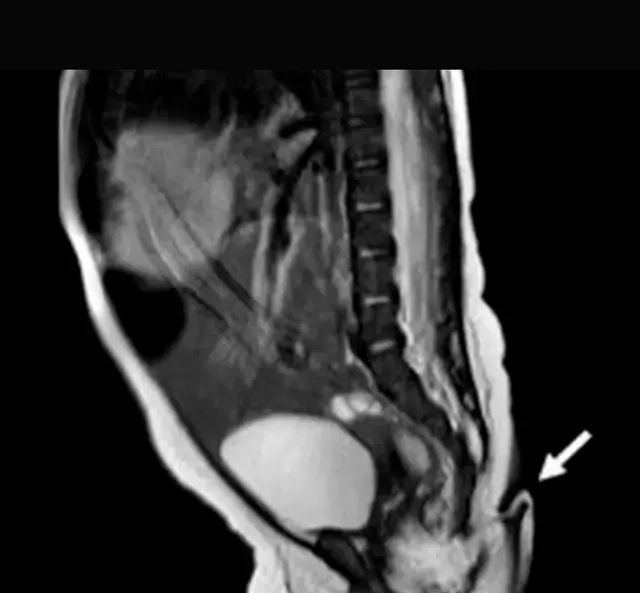

Radiografías a la pequeña bebé con una extremidad en forma de 'cola' / Foto: Journal of Pediatric Surgery Case Reports

A través del informe, el parto habría procedido por una cesárea en un hospital rural, sin embargo, se habría dado con total normalidad. Luego, las radiografías posteriores mostraron con exactitud la extremidad 'extra' de la pequeña

Por otro lado, los exámenes descartaron irregularidades o estructuras óseas dentro de la cola, así también, a través de resonancias magnéticas se rechazó la posibildiad de una anormalidad cerebral.

Se sabe que 'la cola de la bebé' tenía carne con tejido blando, arterias, venas y terminaciones de nerviosas. Tras el seguimiento a la recién nacida, los médicos optaron por la cirugía, dado que esta extremidad creció un 0.8 centímetros.

Es así que la cola fue retirada en cirugía sin dejar secuela alguna en la infante. Previamente, se decartó cualquier tipo de irregularidad con el sistmea nervioso. Según el Journal of Pediatric Surgery Case Reports, la pequeña (no identificada) fue dada de alta y que no se registraron complicaciones en su seguimiento.